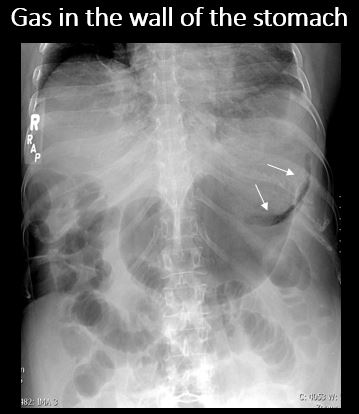

There is air in the wall of the stomach. |

No | NA |